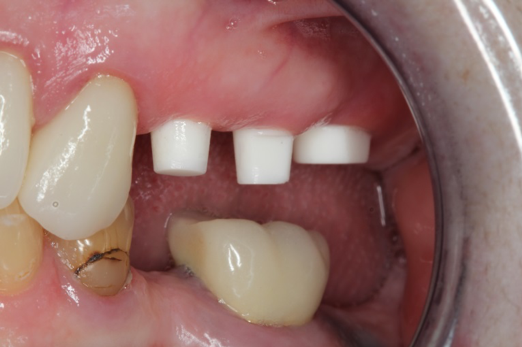

Fig 12. Ceramic implants placed and sutured.

Figure 12

Fig 13. Lateral view after placement.

Figure 13

Figure 10 through Figure 13 show the preoperative x-ray and the sequence of beginning with healed sites through the surgical placement of the implants. The implants were protected by an Essix-style wound-protection removable retainer for approximately 12 weeks. After the integration phase, the implants and the natural dentition were prepared using traditional crown-and-bridge high-speed diamond and zirconia cutting burs to remove decay and existing restorative materials, to complete and refine the natural-tooth structures to receive full-crown coverage, and to prepare and refine gingival margins of the zirconia implants where needed.